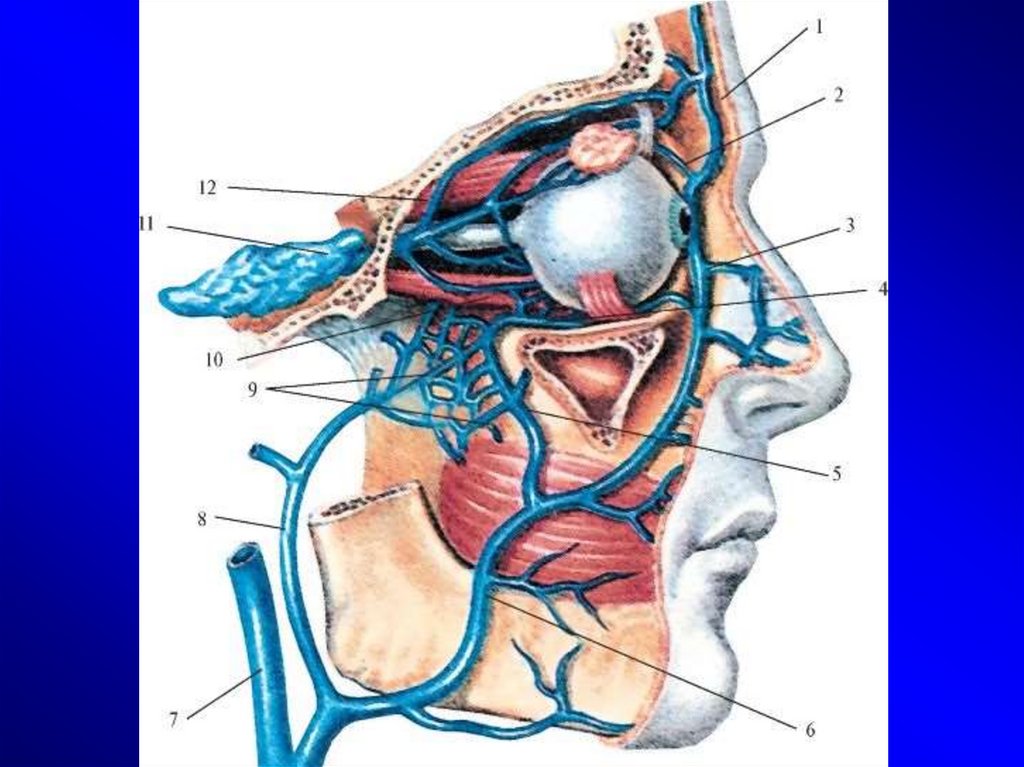

Анатомия внутренней яремной вены: КТ изображения